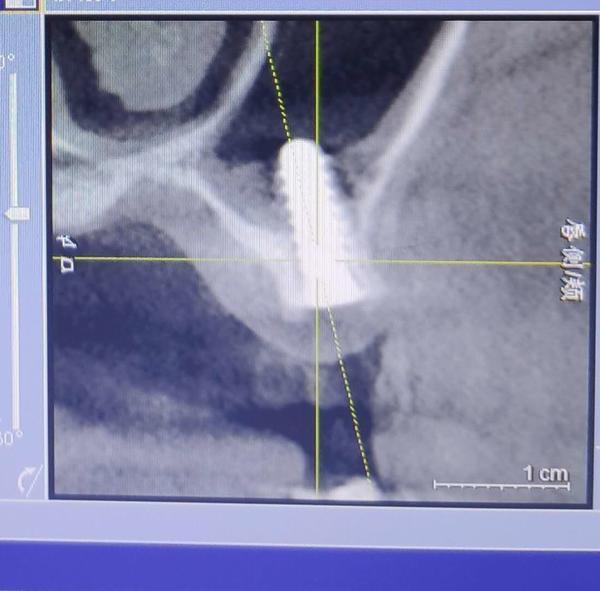

2019年下半年,在出現(xiàn)了不適反應(yīng)后,葉女士到沈陽(yáng)一家部隊(duì)醫(yī)院口腔門診求醫(yī)。經(jīng)CT等檢查,她才發(fā)現(xiàn),原來(lái)有一顆種植體已經(jīng)進(jìn)入了她的上頜竇腔。

葉女士做出的影像檢查結(jié)果顯示,其中一顆植體已經(jīng)進(jìn)入上頜竇腔內(nèi)。

“有大醫(yī)院醫(yī)生告訴我,這就是說(shuō),種植體把我上頜竇腔打穿,口腔和鼻腔連通了!”葉一帆說(shuō),她隨后了解得知,袁克偉并不具備種植牙的技術(shù)水準(zhǔn),而且執(zhí)業(yè)地點(diǎn)也不在天麗口腔,且天麗口腔診所也不具備種植牙這一診療項(xiàng)目,“我是被他當(dāng)成小白鼠了”。

2019年7月,在出具的診斷證明上,沈陽(yáng)市當(dāng)?shù)匾患胰揍t(yī)院的知名口腔診療專家說(shuō),該種植體已經(jīng)進(jìn)入上頜竇腔,需要取出。